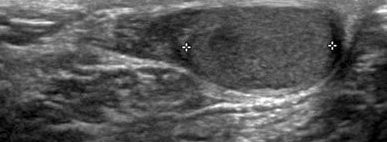

Right orchiectomy specimen. Atrophy of the testicular parenchyma is evident (Courtesy Dr. V. Penopoulos)